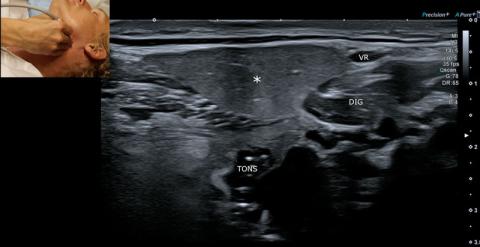

LYMFEKNUDER

Ved skanning af halsen vil der ses multiple normale lymfeknuder som en velafgrænset bønneformet/oval struktur med homogen hypoekkoisk cortex og let hyperekkoisk hilus (Figur 2). UL-skanning af lymfeknuder bruges oftest til diagnosticering af en eventuel abscedering hos børn eller til udelukkelse af malignitet (metastase eller lymfom). Lymfeknudemetastasering ses ofte i bestemte levels af halsen (Figur 1), og kan derfor også bruges til at guide diagnostik af en primærtumor. Fjernmetastaser til lymfeknuder på halsen kan forekomme fra lunger og abdomen og skal især mistænkes ved fund af en malignitetssuspekt lymfeknude i level 5 [8]. Man skal havde mistanke om malignitet ved fund af en forstørret lymfeknude (≥ 8 mm i korteste aksiale mål), rund form (bredde-højde-ratio < 2), manglende hilus, intranodal nekrose, uskarp afgrænsning, perifert flow, kalcificering eller pseudocystisk morfologi [9]. En enkelt af ovenstående karakteristika er ikke specifik for malignitet, men skal indgå i den samlede diagnostik.

Reaktive lymfeknuder kan ses med let forstørret hypoekkoisk oval form med bevaret hilus, men afgrænsningen kan være lidt utydelig pga. periadenitis. Vær opmærksom på, at lymfeknuder i relation til gl. submandibularis naturligt kan have en mere rund form, og at reaktive lymfeknuder hos børn ofte kan blive meget store (> 2 cm i største diameter) [10]. Desuden kan et hyperekkoisk hilus ikke altid visualiseres med B-mode-UL-skanning, hvorfor der i stedet skal tilføjes Doppler for at undersøge vaskulariseringen af hilus. Ved en abscederet lymfeknude er der manglende hilus (hypoekkoisk/anekkoisk center uden flow), hvortil der ofte ses hypervaskularisering af periferien og det omgivende inflammerede væv [11] (Figur 2).

Planocellulære karcinomer udgående fra slimhinderne er den hyppigste hoved-hals-cancer [12]. Metastasering til de regionale lymfeknuder forekommer hyppigt og har betydning for valg af terapi, hvorfor UL-skanning af halsen er vigtig som led i stadieinddeling [9]. Metastaser af planocellulært karcinom ses runde og udtalt hypoekkoiske eller cystisk/nekrotiske med skarp afgrænsning til omkringliggende væv, mens diffus afgrænsning tyder på kapselgennemvækst. Hilus er ofte manglende, og ved Dopplerundersøgelse ses der perifer vaskularisering, men maligne lymfeknuder kan også have samtidigt bevaret hilusvaskularisering [13]. Mikrokalcifikationer ses sjældent ved planocellulært karcinom, og metastase fra et papillært eller medullært thyroideakarcinom skal i stedet overvejes som differentialdiagnose. Lymfom (oftest non-Hodgkin) skal mistænkes ved multiple forstørrede, runde, hypoekkoiske lymfeknuder i level 2-5 og skarp afgrænsning [14].